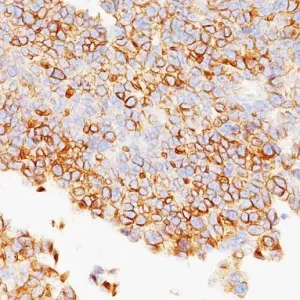

Bladder